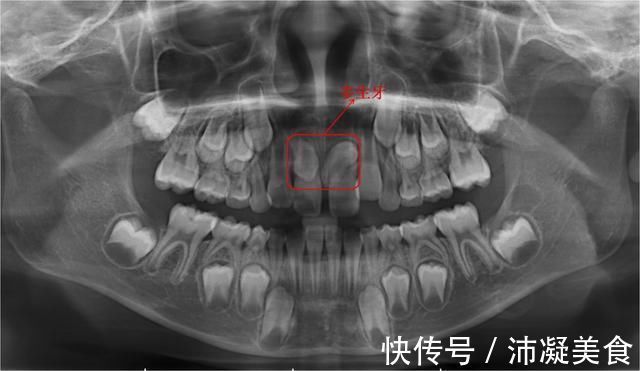

4、长牙齿

有时在两个正常恒齿胚胎之间会长出1~2个多生牙。多生牙不仅影响正常恒牙的顺利发芽,而且时间过长还可以含有牙囊肿。